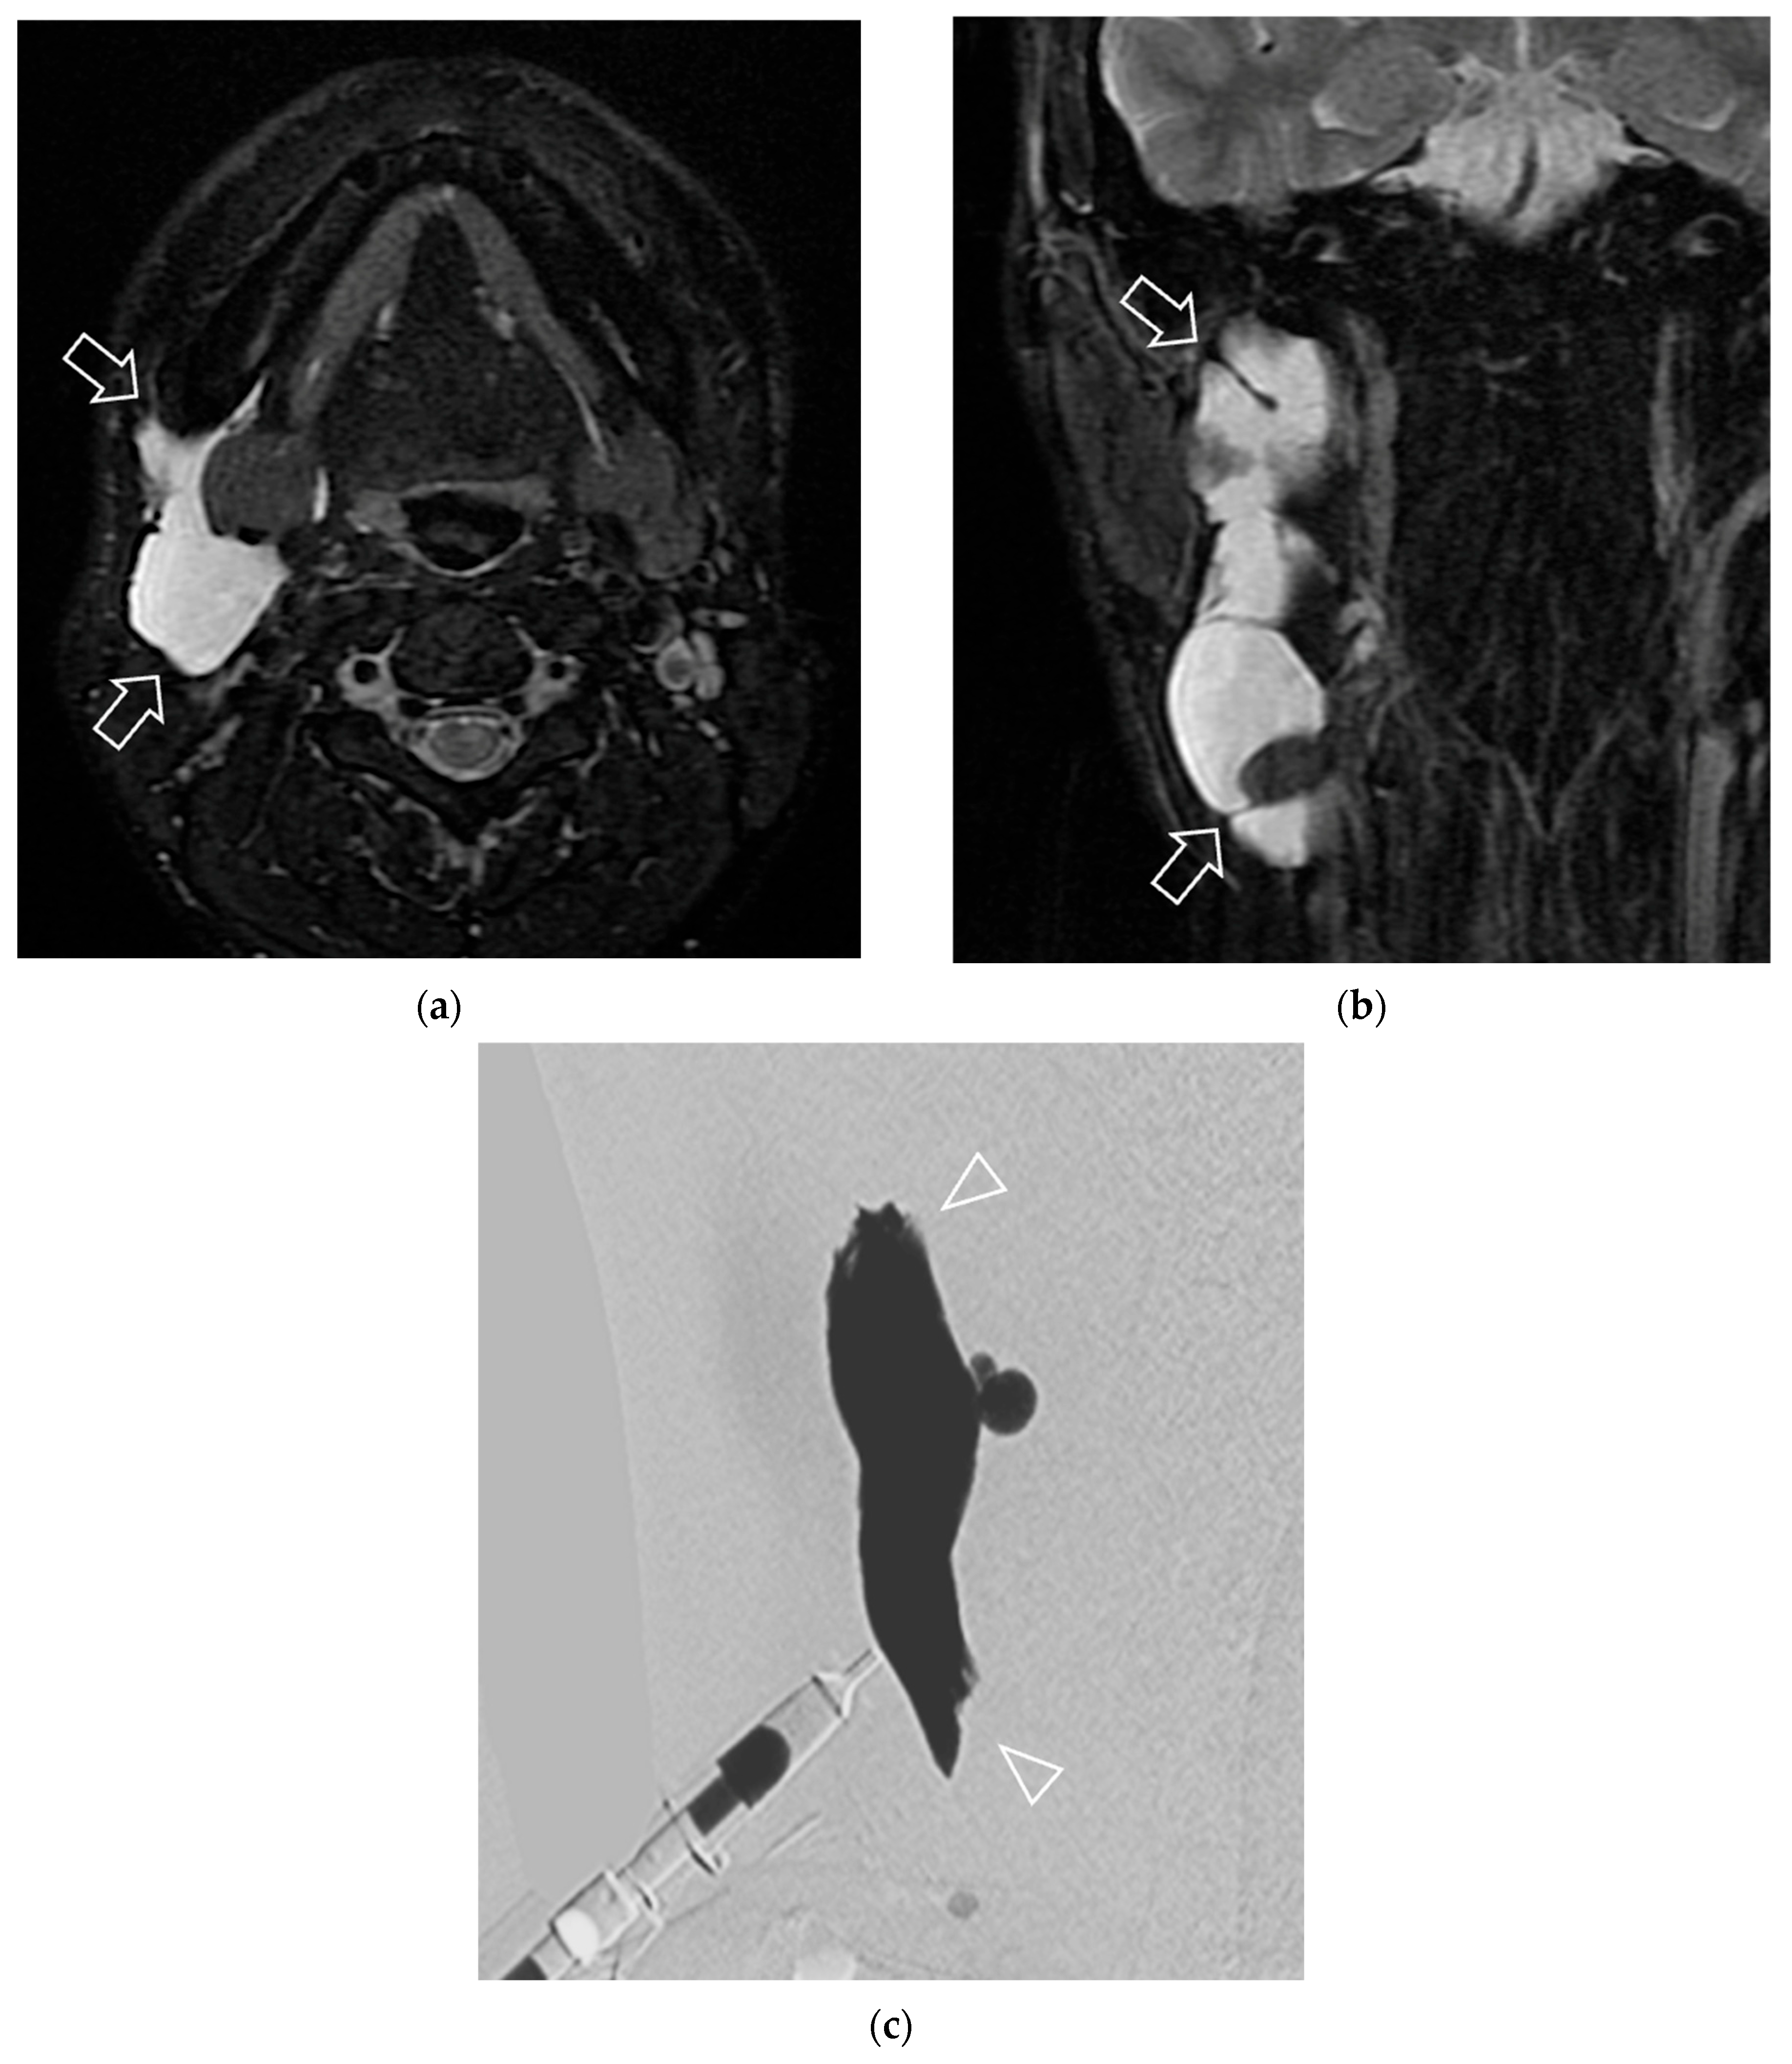

2.3. Treatment Protocol of Bleomycin Sclerotherapy

2.5. Data Collection